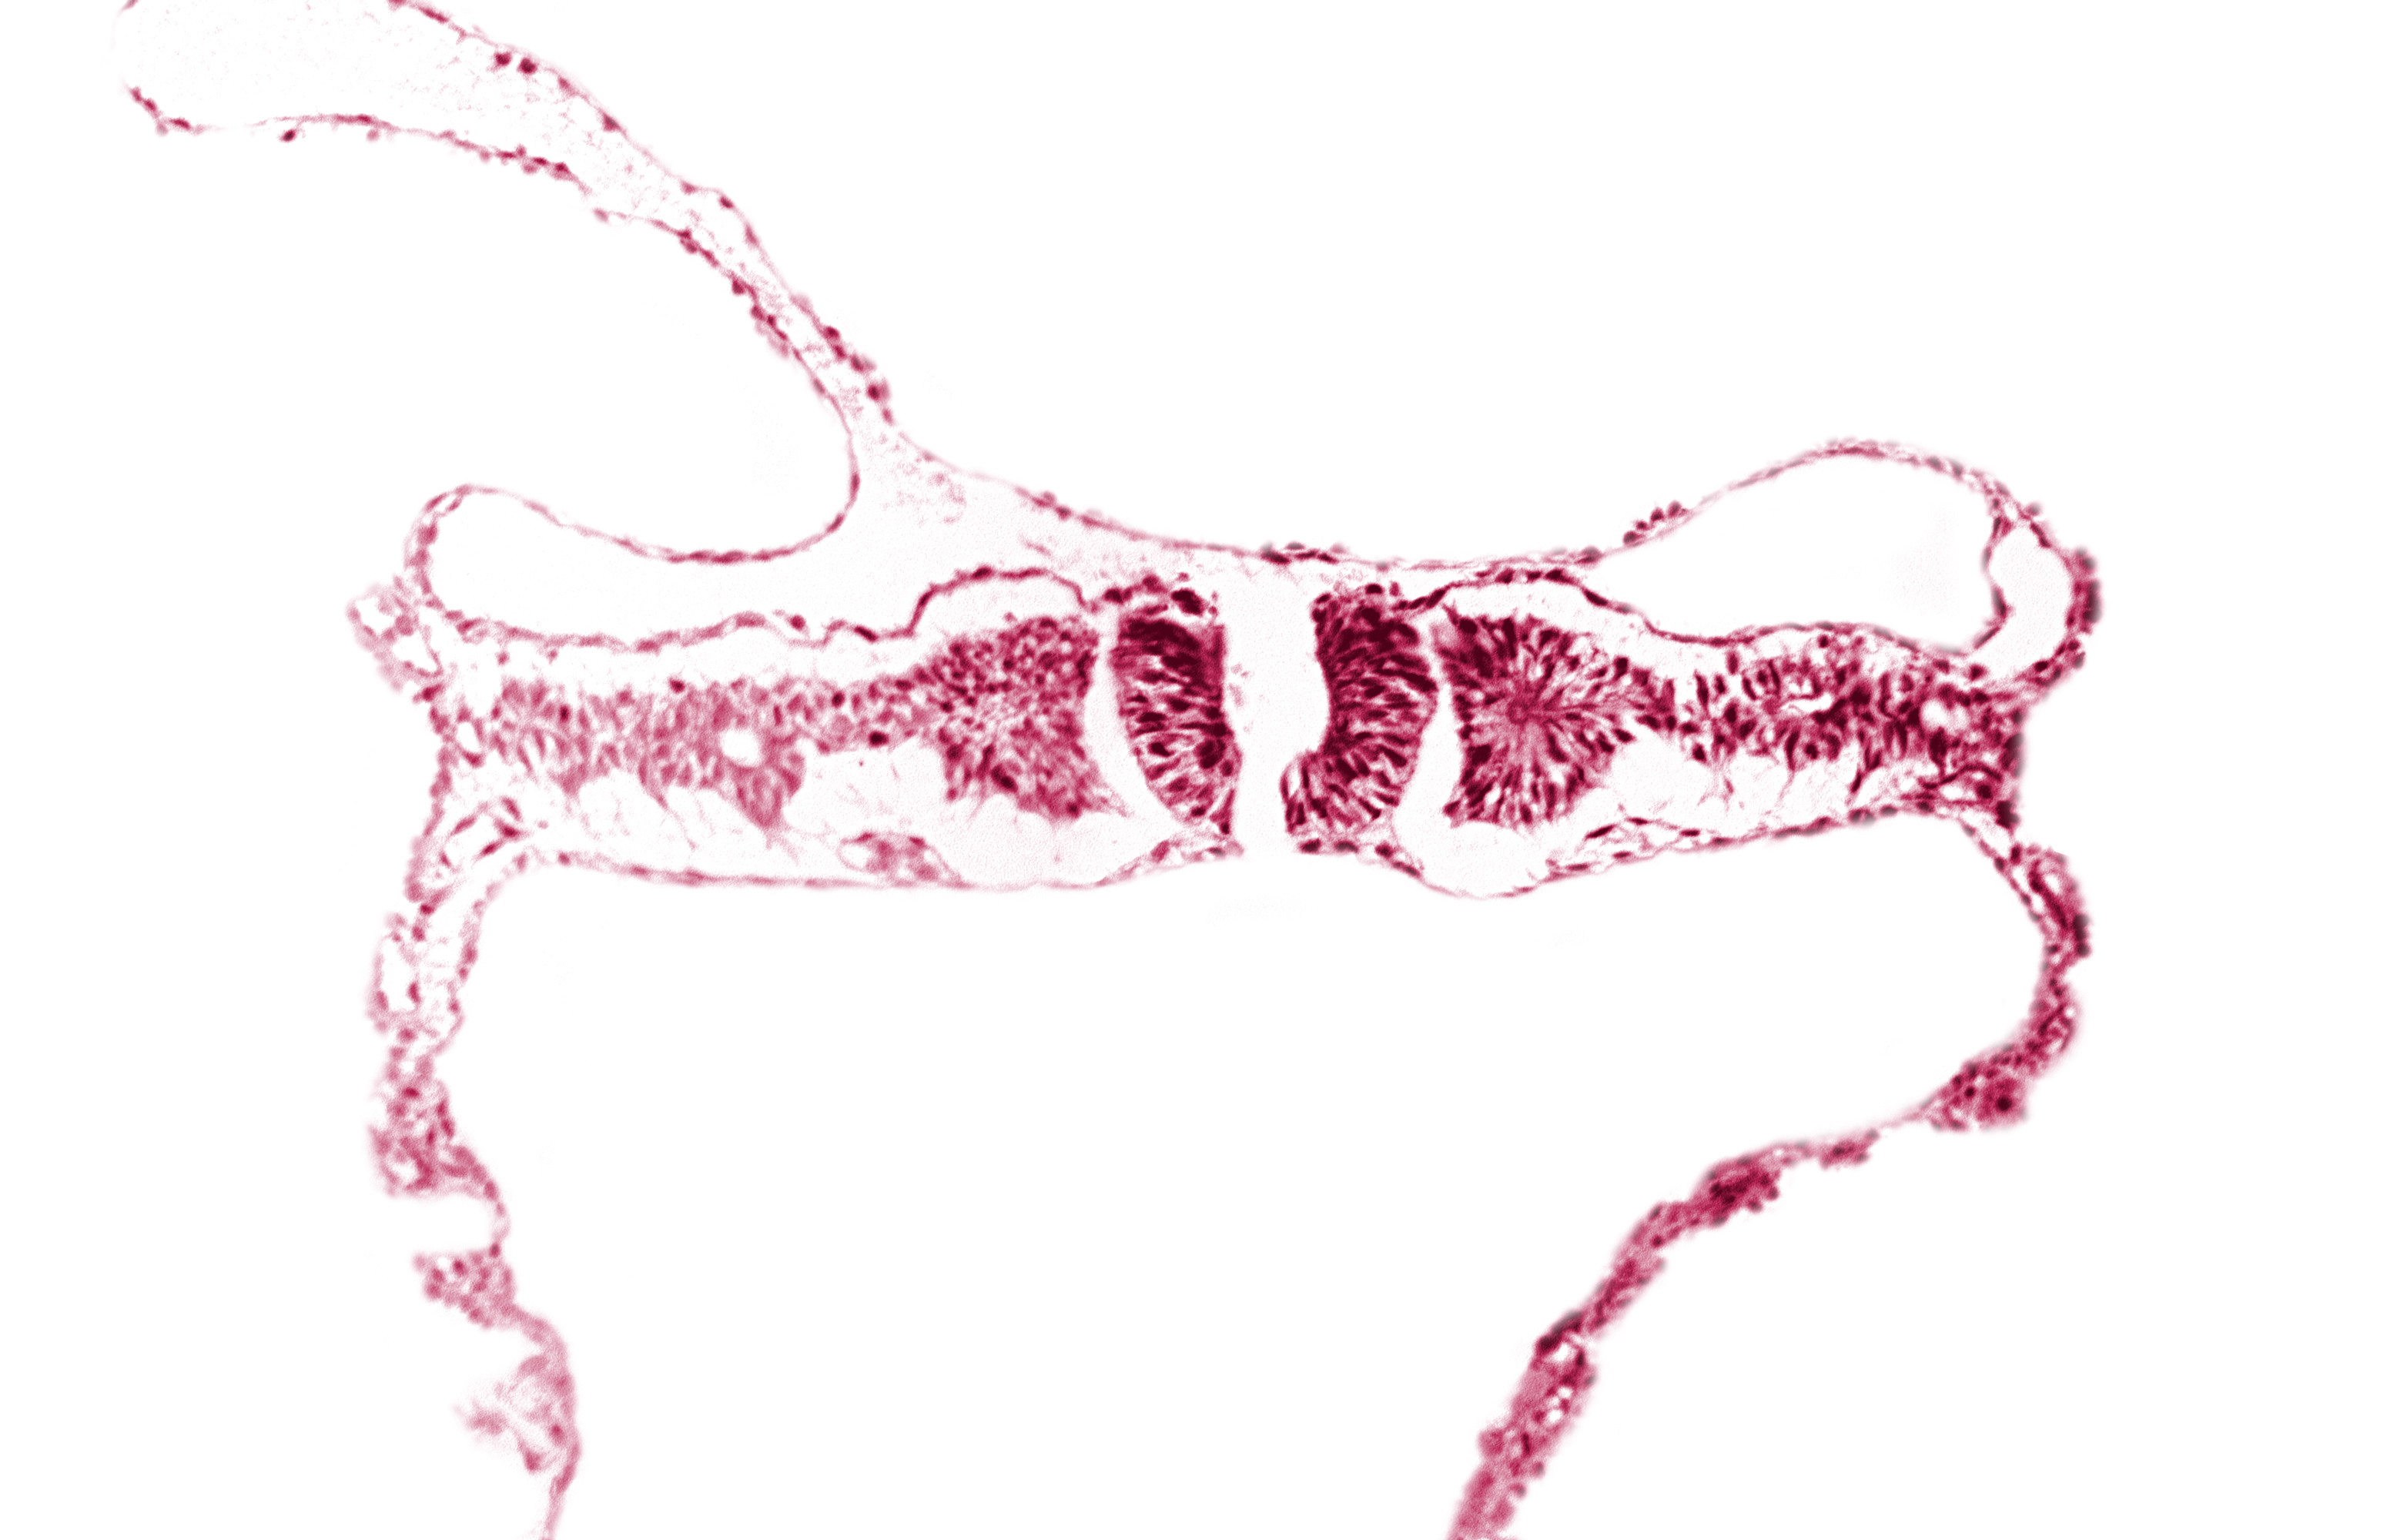

Carnegie Embryo #6330   |   Location: 02-06-11

Keywords: amniotic cavity, artifact separation(s), extra-embryonic coelom, intermediate mesenchyme, midgut, primordial peritoneal cavity, somite 5 (C-1), umbilical vesicle cavity

Source: The Virtual Human Embryo.